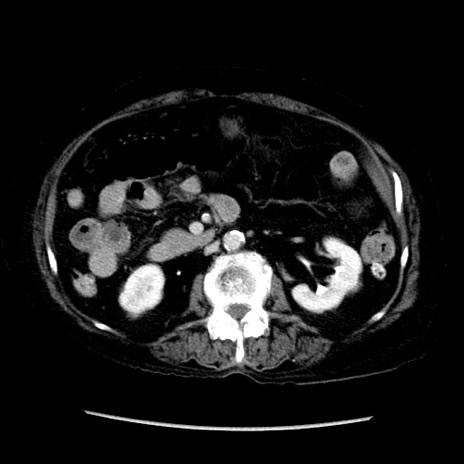

症例14(横断像)

【症例】 90歳代女性

【主訴】 腹痛・嘔吐

【現病歴】今朝から左側腹部痛を認めた。 経過観察していたが、嘔吐を認めたため来院。

【既往歴】 子宮癌術後

【身体所見】 意識清明、BP 127/54mmHg、P 98bpm Sp02 95%(RA)、BT 35.8°C、腹部平坦・軟腸ぜん動音聴取良好、右下腹部圧痛(+) 反跳痛なし

【データ】WBC 9800、CRP 0.46